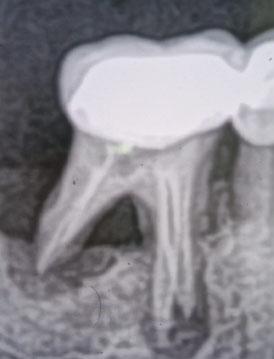

Dental X-Ray Showing Bone Infection and Abscess Case Analysis

The dental X-ray shows bone changes around the roots of the teeth, particularly in the back tooth area. There are visible signs of bone loss and darkened areas near the root tips, which commonly indicate a tooth abscess or chronic dental infection.

Some teeth appear previously treated, but the surrounding bone suggests ongoing or unresolved infection.